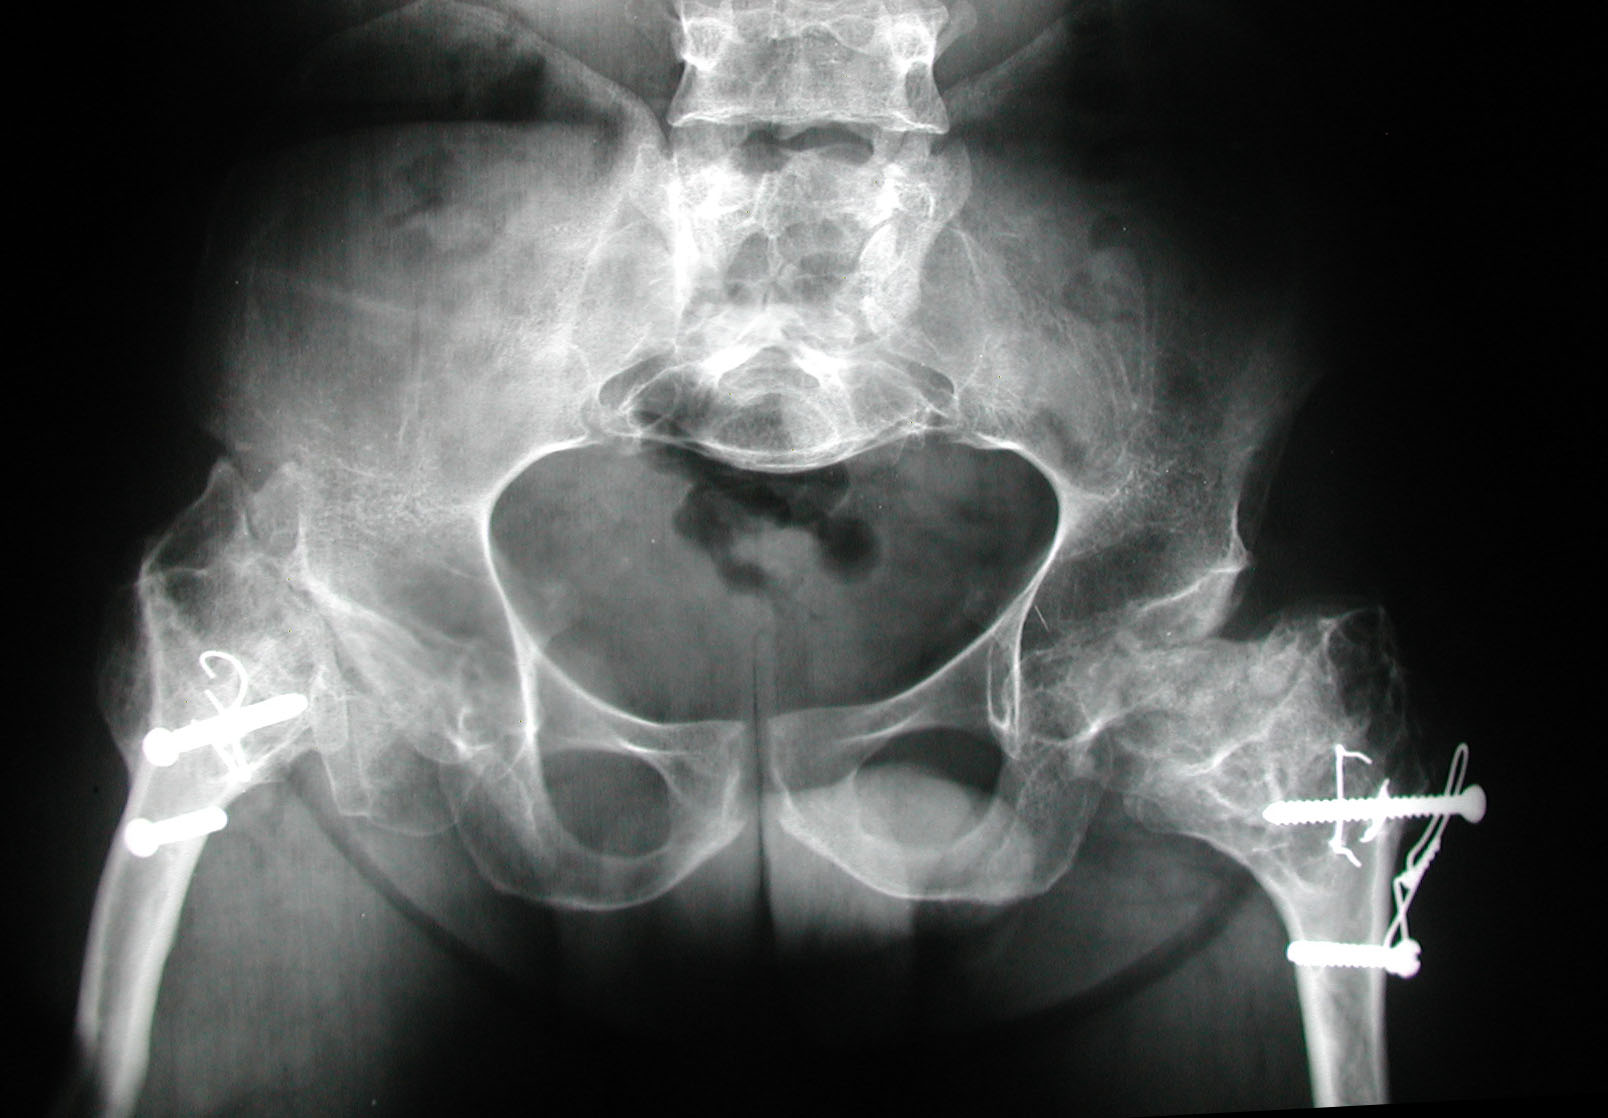

Wirtz DC, Birnbaum K, Sievert CH, Heller KD. Bilateral total hip replacement in pseudoachondroplasia. Acta Ortop Belg

;66(4):407-8.

Sekundiak TD. Total hip arthroplasty in patients with dwarfism. Orthopedics 2005;28(9):1075-8.

Chiavetta JB, Parvizi J, Shaughnessy WJ, Cabanela ME. Total hip arthroplasty in patients with dwarfism. J Bone Joint Surg

Am 2004;86:298-303.

Ain MC, Andres BM, Somel DS, Fishkin Z, Frassica FJ. Total hip arthroplasty in skeletal dysplasias. Patients selection,

preoperative planning, and operative techniques. J Arthroplasty 2004;19(1):1-7.